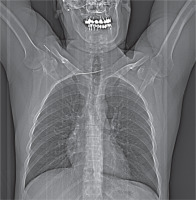

On radiological evaluation on chest X-ray a broken K-wire was observed with the distal part in the clavicle and the proximal part migrated into the thorax (Figure 1). Computed tomography revealed that part of the broken wire lay transversely across the spinal canal at the level of Th1. The length of this part was 7.0 cm, with the tip in the right mediastinum, posterior to the superior vena cava (Figures 2 A, B).